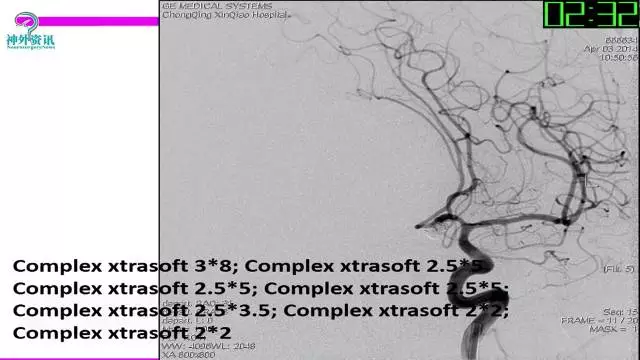

今天为大家分享的是“强生医疗CNV-神经介入专栏”第三十六期,由重庆第三军医大学附属新桥医院神经外科刘俊带来的“Galaxy弹簧圈在不规则动脉瘤中的临床应用”精彩讲课视频及PPT,欢迎观看。文章仅代表作者个人观点,如有不同见解,欢迎同道斧正!